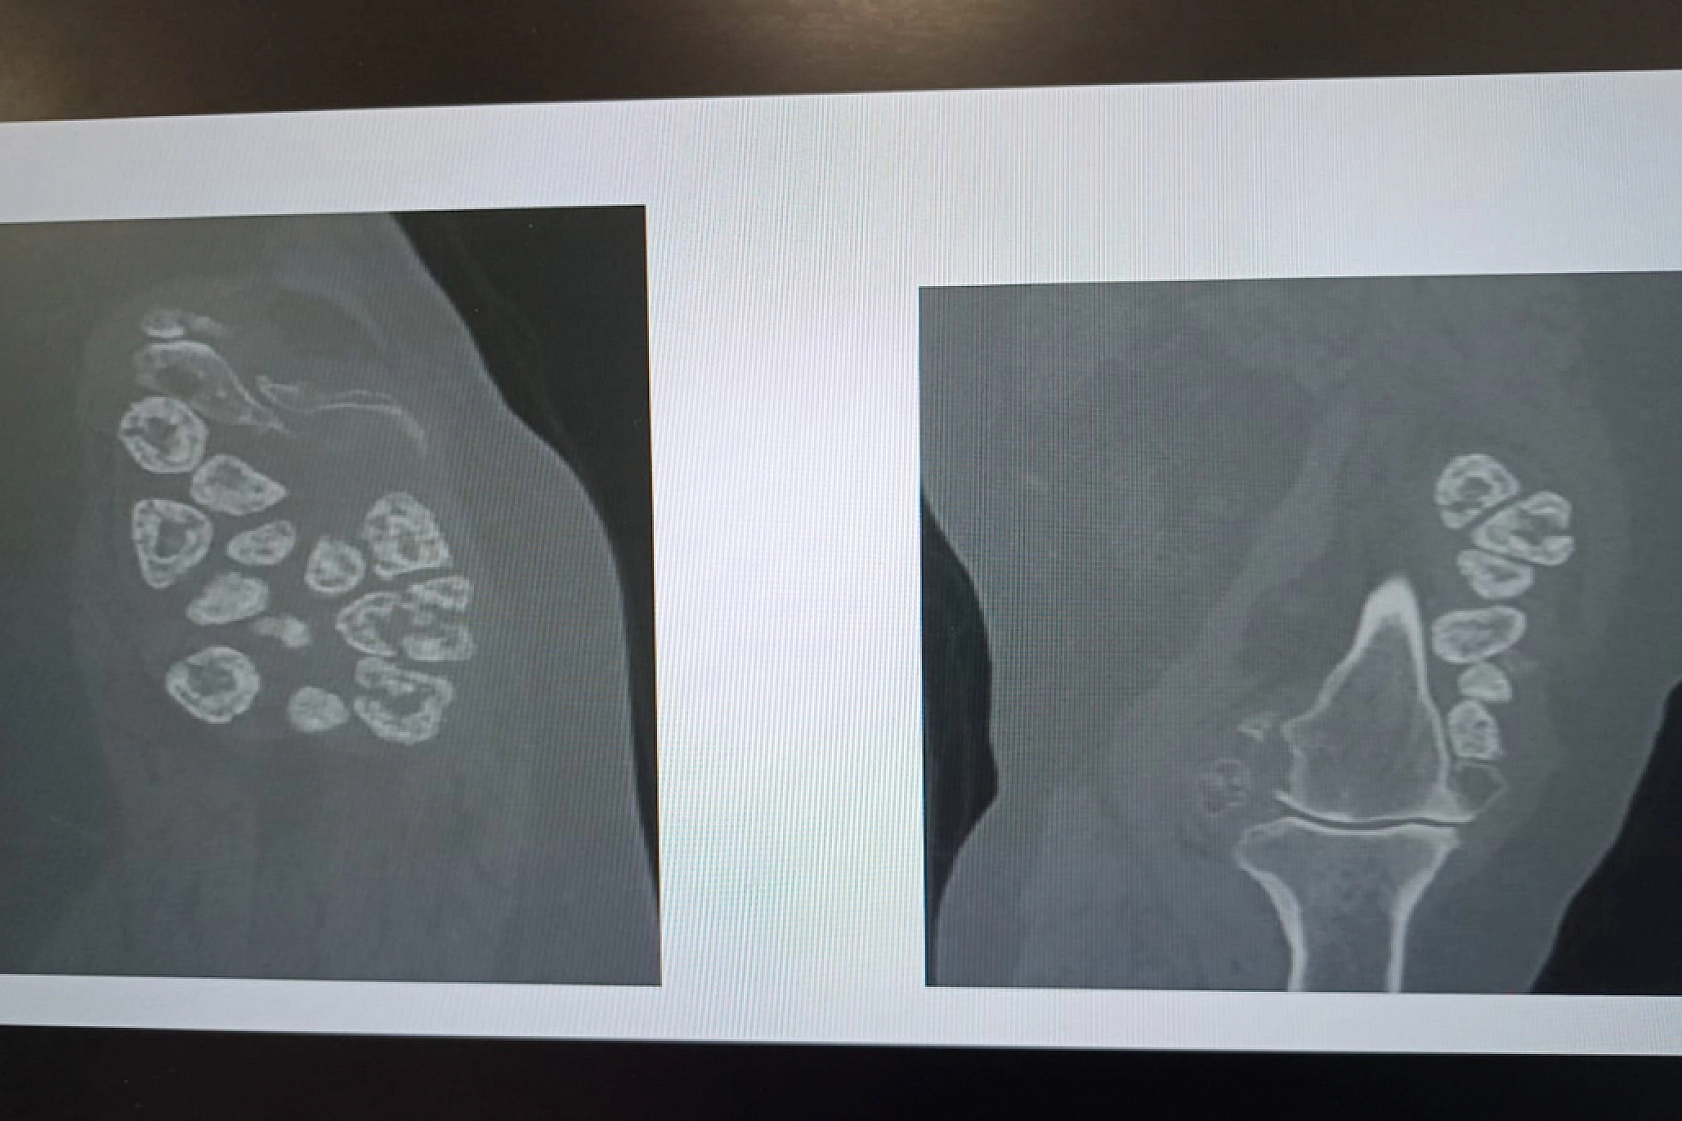

Malatya'da diz ağrısı ve hareket kısıtlılığı şikayetiyle hastaneye başvuran 73 yaşındaki Elif Büyükbirer'in dizinden, yapılan ameliyatta 24 adet taşlaşmış tümör çıkarıldı.